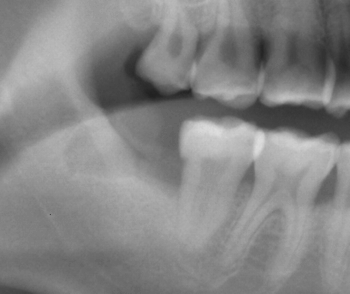

2分割するだけで、案外と簡単に抜けました! |

今回は、歯の「頭」と「尻尾」に切断すると簡単に抜けましたが…

場合によっては2本足が開いていたり、足が曲がっていたりとやっかいな事も多いです、、、やっかいなパターンはまた次回に・・・